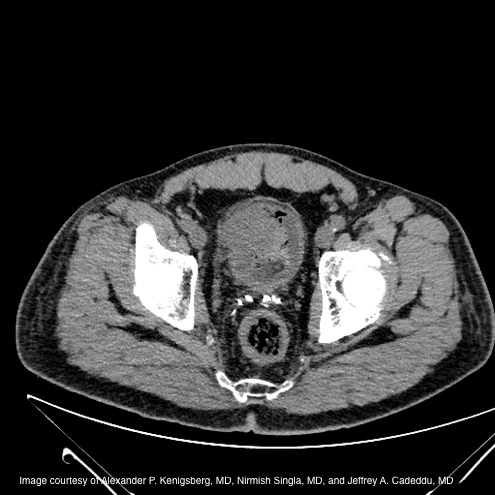

A CT urogram is obtained (figure 1). Imaging reveals a heterogeneous 4cm enhancing mass at the right aspect of the bladder anterolaterally, with some stranding changes noted in the fat adjacent to this lesion. No hydronephrosis, pelvic lymphadenopathy, or sites of metastatic disease are found.

Figure 1. Large anterior enhancing bladder mass on CT urogram